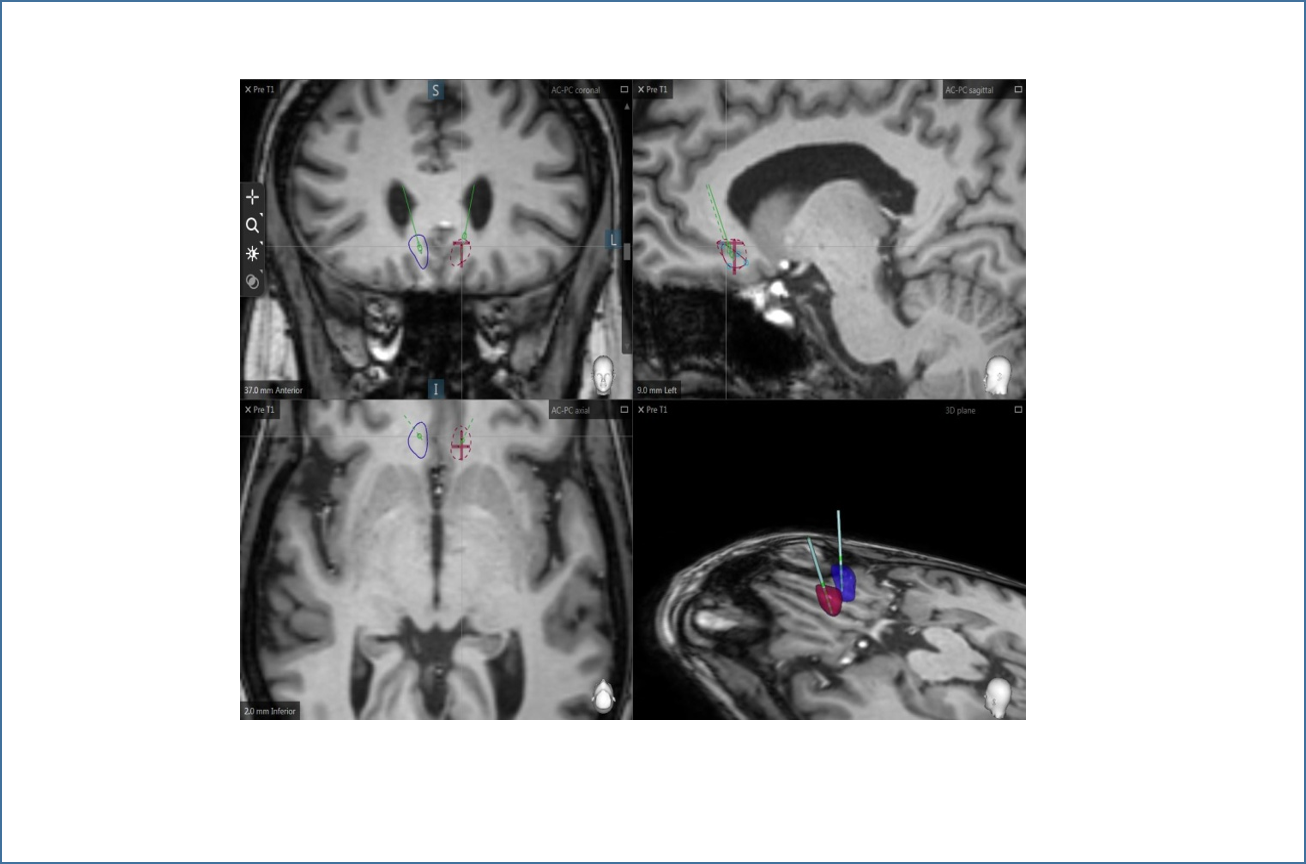

Realizan el primer estudio en el que se aplica la estimulación cerebral profunda (DBS) en pacientes con esquizofrenia resistente al tratamiento